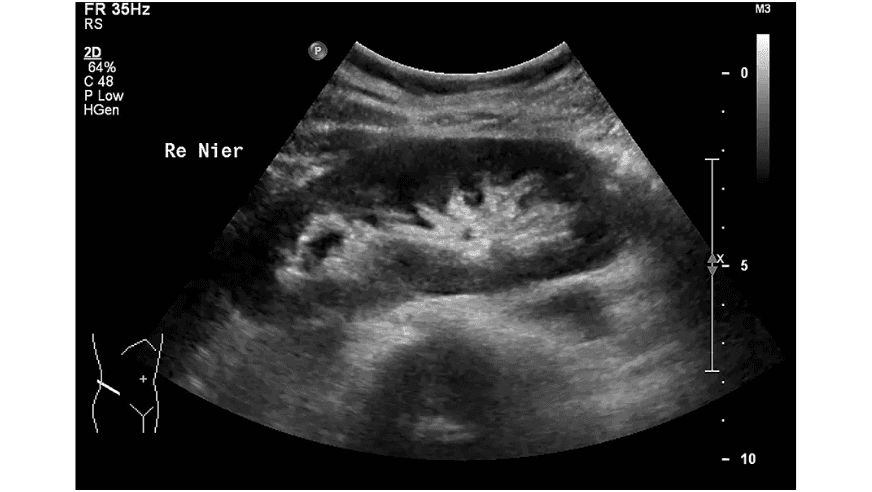

Bloedonderzoek bij nierschade

Je bloed wordt vooral onderzocht op kreatinine (ook wel: creatinine). Dit is een afvalstof van de spieren. Nieren halen kreatinine uit het bloed. Zit er veel kreatinine in je bloed? Dat kan betekenen dat er nierschade is.